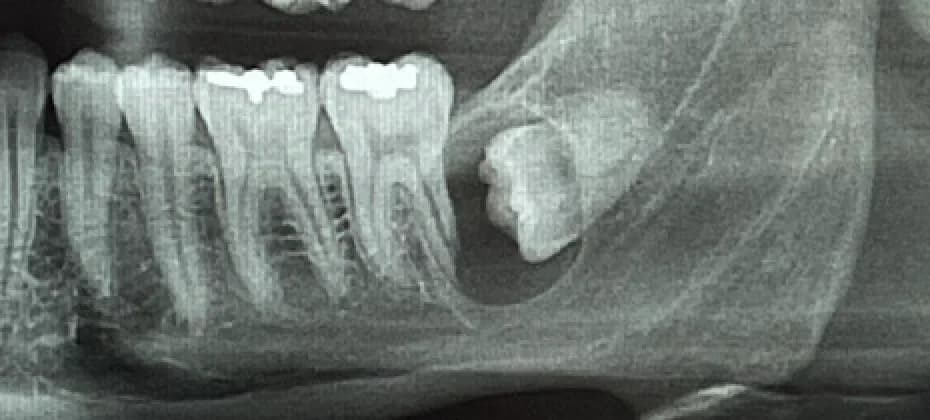

L'extraction des dents de sagesse, également appelées troisièmes molaires, est une procédure dentaire courante effectuée pour enlever les dents qui ne peuvent pas pousser correctement ou qui causent des problèmes dentaires. Elles sont généralement du nombre de quatre et font habituellement leur apparition en bouche entre l’âge de 15 et 25 ans. Elles peuvent faire complètement éruption, être partiellement éruptées ou incluses. Elles n’ont généralement pas assez de place dans la bouche. Ce faisant, elles sont très souvent mal alignées et exercent des pressions sur les dents adjacentes, pouvant même les endommager. L'extraction des dents de sagesse est souvent recommandée lorsque les dents sont incluses (piégées dans la gencive ou l'os) ou qu'elles causent des problèmes tels que la douleur, l'infection, la carie dentaire, le déplacement des autres dents ou le développement de kystes. Il est conseillé de procéder à leur extraction à un jeune âge, généralement à la fin de l’adolescence ou au début de l’âge adulte. Effectivement, les risques s’accroissent avec l’âge et la convalescence est plus aisée à un jeune âge.